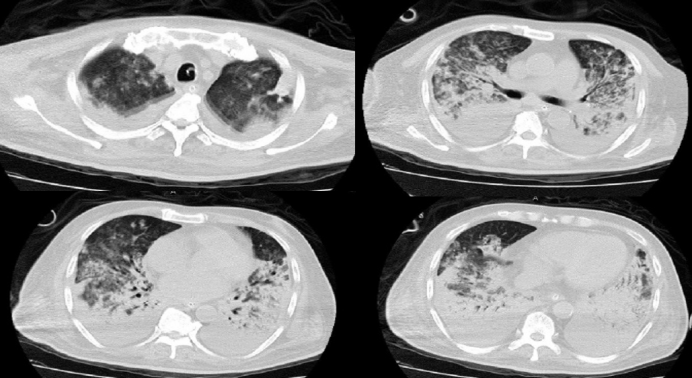

病例5:63岁女性患者,因呼吸困难20天、加重1天入院患者20天前无明显诱因出现活动性气促,伴心悸、咳嗽、咳白痰;1天前患者呼吸困难症状加重,稍行走5米后即气促严重;指脉氧饱和度72%,氧合指数64.2 mmHg(HFNC:流量55 L/min,吸氧浓度95%),查肿瘤指标CEA>1000 ng/ml予气管插管机械通气。床旁纤支镜可见气管膜稍充血,未见明确新生物,分泌物少病理提示红细胞背景中见大量腺癌细胞,免疫组化符合肺腺癌。患者诊断为肺腺癌伴纵隔淋巴结、双肺内及胸腰椎多发转移。基因检测结果提示存在EGFR经典突变(19外显子缺失)。给予靶向治疗联合抗感染、营养支持及免疫调节等治疗,患者气促明显改善,胸部CT示双肺多发病灶显著吸收(图8)1周后拔管脱机,2周后出院,逐步恢复居家生活,目前仍在长期门诊随访

图片

8  患者治疗前后胸部CT对比

病例6:68岁男性患者,发现肺部占位1年,气促1月,加重伴吞咽困难2天入院。外院胸部CT提示右肺下叶背段占位,双侧肺门及纵隔多发肿大淋巴结,气管、食管中下段明显受压(图9),肿瘤指标NSE 213 ng/ml。入院次日憋喘加重、呼吸衰竭,转入RICU插管上机。纤支镜检查示隆突粗钝,左下叶支气管开口外压性重度狭窄,右主支气管及右中间支气管外压性中度-重度狭窄,管腔内大量白色泡沫状分泌物。予活检、毛刷及右主支气管+右中间支气管镍钛记忆合金覆膜支架置入,同时经超细胃镜引导鼻空肠管置入改善营养;后续完善病理诊断为右肺小细胞肺癌并肺门、纵淋巴结转移免疫治疗联合化疗,支架入后2天拔管,序贯高流量湿化氧疗,4天后转至普通病房,7天后纤支镜检查示(图10):左下叶支气管开口外压性重度狭窄, 支气管镜可进入背段及基底段, 右主支气管、右中间支气管支架在位, 其近端平隆突, 远端平中下叶支气管开口, 管腔通畅, 支架内黏附较多黄白色稠分泌物, 右上叶支气管开口被支架遮挡10天后好转出院, 目前定期返院治疗。

9  患者治疗前胸部CT

10  支架置入1周后纤支镜检查所见